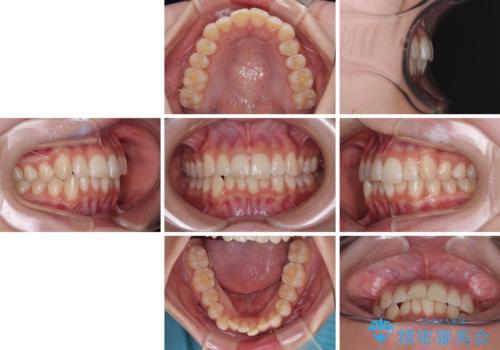

気になる前歯と咬み合わせを改善 インビザライン・モデレート

- 上下前歯の重なりを気にして来院された患者様です。

安価なインビザラインパッケージを用いての治療を希望されており、デコボコの程度が中等度であったため、インビザライン・モデレートを用いて矯正治療を行うこととしました。

インビザライン・モデレートは、製作できるアライナーの枚数に制限があるため、移動可能な量に限りがあるものの、インビザライン・ライトよりも枚数が多いため、幅広い症例に対応可能です。